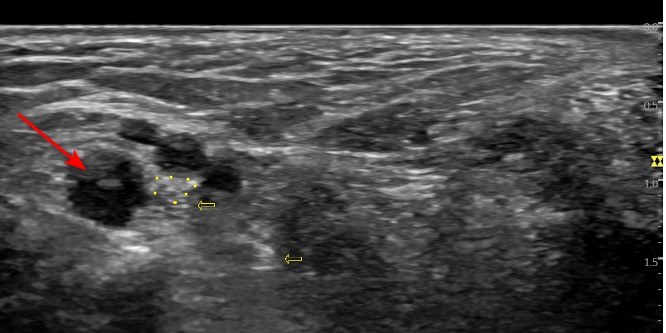

정상 경혈의 초음파 영상 이 부분은 경혈 초음파상 발목 터널 안쪽에 후경골신경의 분지와 후경골동맥, 정맥이 보여야 하는데

환자분의 수천혈 초음파 해당 환자분은 까만 물혹(빨간 화살표)이 보입니다.

경혈 초음파로 살펴보니 거골하관절로 연결된 것이 보입니다. 예전에도 관절염으로 물이 차서 결절종을 제거했던 적이 있으셨다고요. ## 이렇게 딱딱한 물혹이 터널 안에서공간을 차지하면서 발바닥신경을 압박하고 있는데지압한다고 꾹꾹 눌러대니증상이 악화되는 것은 당연하겠죠? 더군다나 평발로 발의 아치가 무너져있는데 오래 서있으니까 도수치료, 체외충격파로도 회복하기 어려웠을 겁니다. > 초음파 유도하 도침술 발목 터널의 압력을 빠르게 해결해주는 도침 치료를 시행했습니다. 실시간 초음파로 도침을 확인하면서 신경과 혈관을 피해서 정확하게 시술합니다.